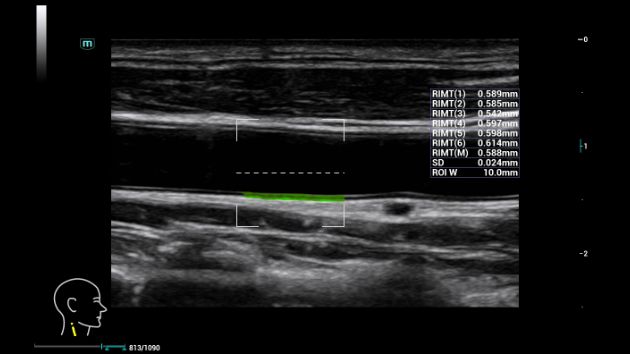

Consona presenta soluzioni nuove e concrete, che aiutano a effettuare diagnosi efficaci con semplicitĂ , rivolgendosi a un'ampia platea di pazienti. La serie mette a disposizione strumenti estremamente avanzati per rimanere all'avanguardia nella diagnosi cardiovascolare.

Galleria di immagini